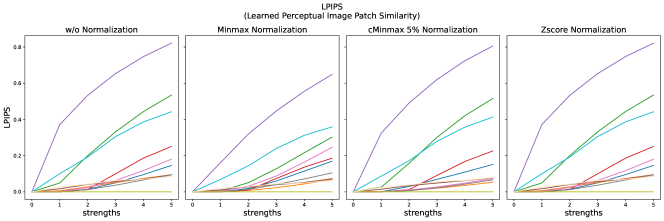

The results for all strengths are given in Figs. A.1-A.4. In Tab. 5 - 8, the results for distortions of maximal strength (s=5) are summarized.

For all applied distortions, all reference metric scores monotonously measure lower similarity for increasing distortion strengths.

Across all normalization methods, all metrics are very sensitive to translation and not very sensitive to replace artifacts.

SSIM similarity scores for strong blurring are very high, compared to most other distortions.

Gaussian noise is better detected with Minmax normalization, while stripe artifacts seem to be less detected with Zscore normalization.

Images distorted with Gaussian blurring and ghosting artifacts receive very high PSNR similarity scores, especially with small distortion strengths.